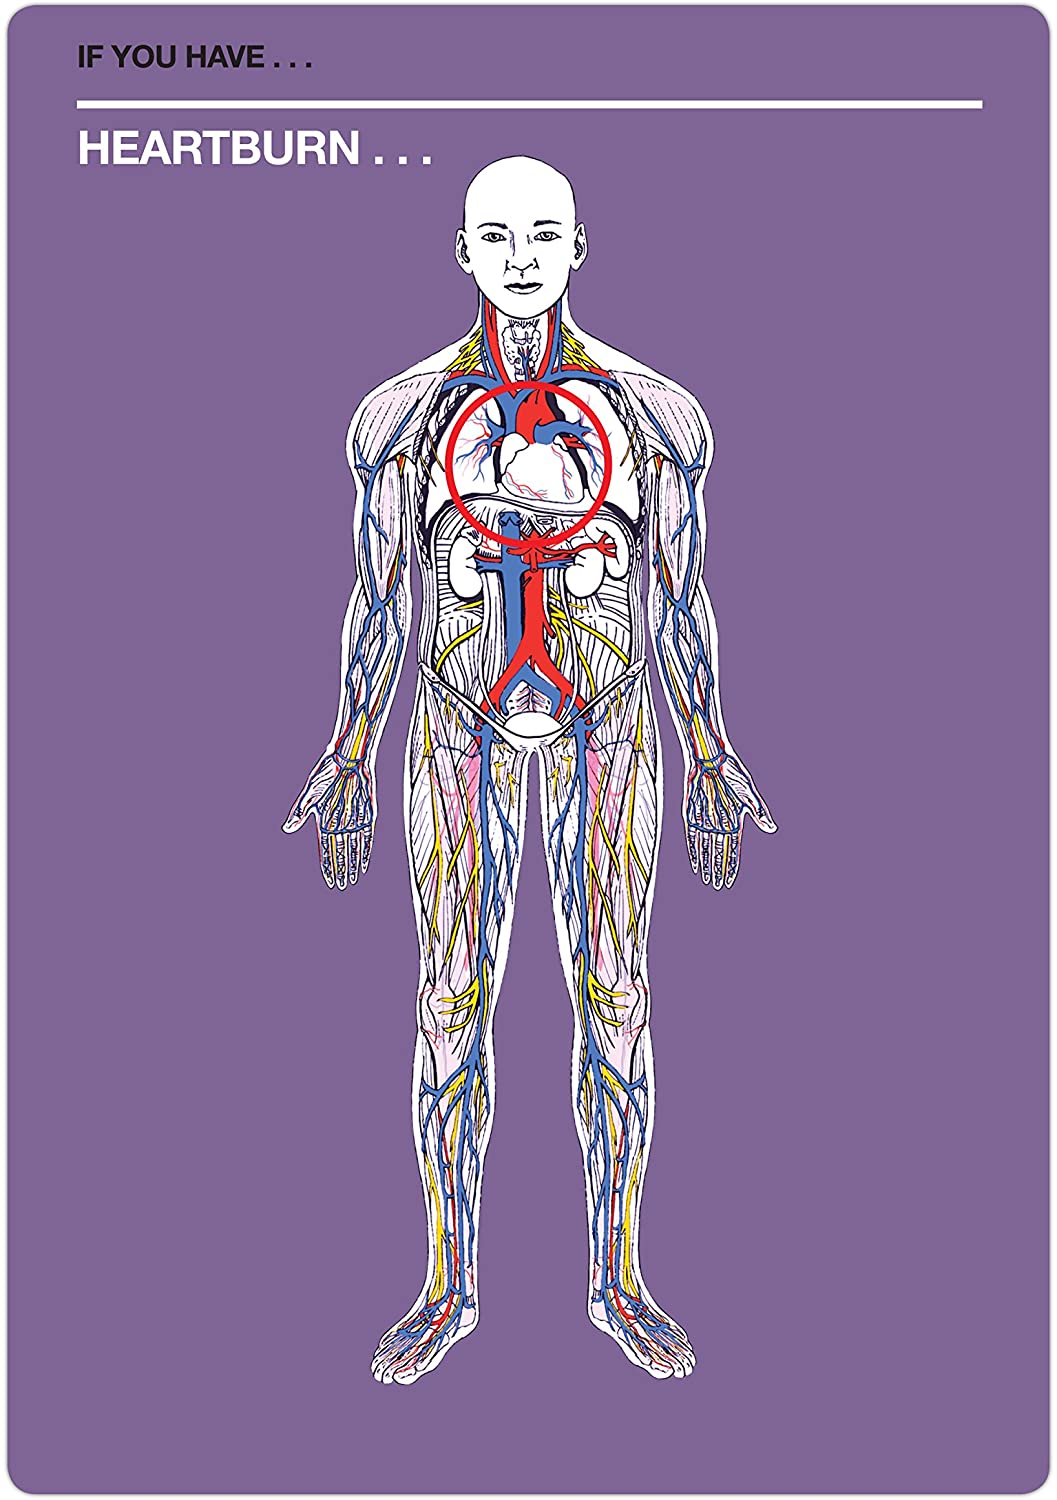

- With this deck of Fifty Things That Might Kill You, pick your symptom and pick a card (or cards) to see what rare, multisyllabic, and possibly fatal disease you might have

- A symptom checker that mixes dark humor (and actual facts) for hypochondriac fun!